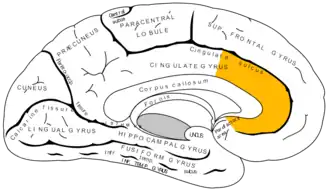

![]() Medial surface of right hemisphere, with Brodmann's areas numbered | |

In human brains, the anterior cingulate cortex (ACC) is the frontal part of the cingulate cortex that resembles a "collar" surrounding the frontal part of the corpus callosum. It consists of Brodmann areas 24, 32, and 33.

Anatomy

The anterior cingulate cortex can be divided anatomically based on cognitive (dorsal), and emotional (ventral) components.[5] The dorsal part of the ACC is connected with the prefrontal cortex and parietal cortex, as well as the motor system and the frontal eye fields,[6] making it a central station for processing top-down and bottom-up stimuli and assigning appropriate control to other areas in the brain. By contrast, the ventral part of the ACC is connected with the amygdala, nucleus accumbens, hypothalamus, hippocampus, and anterior insula, and is involved in assessing the salience of emotion and motivational information. The ACC seems to be especially involved when effort is needed to carry out a task, such as in early learning and problem-solving.[7]